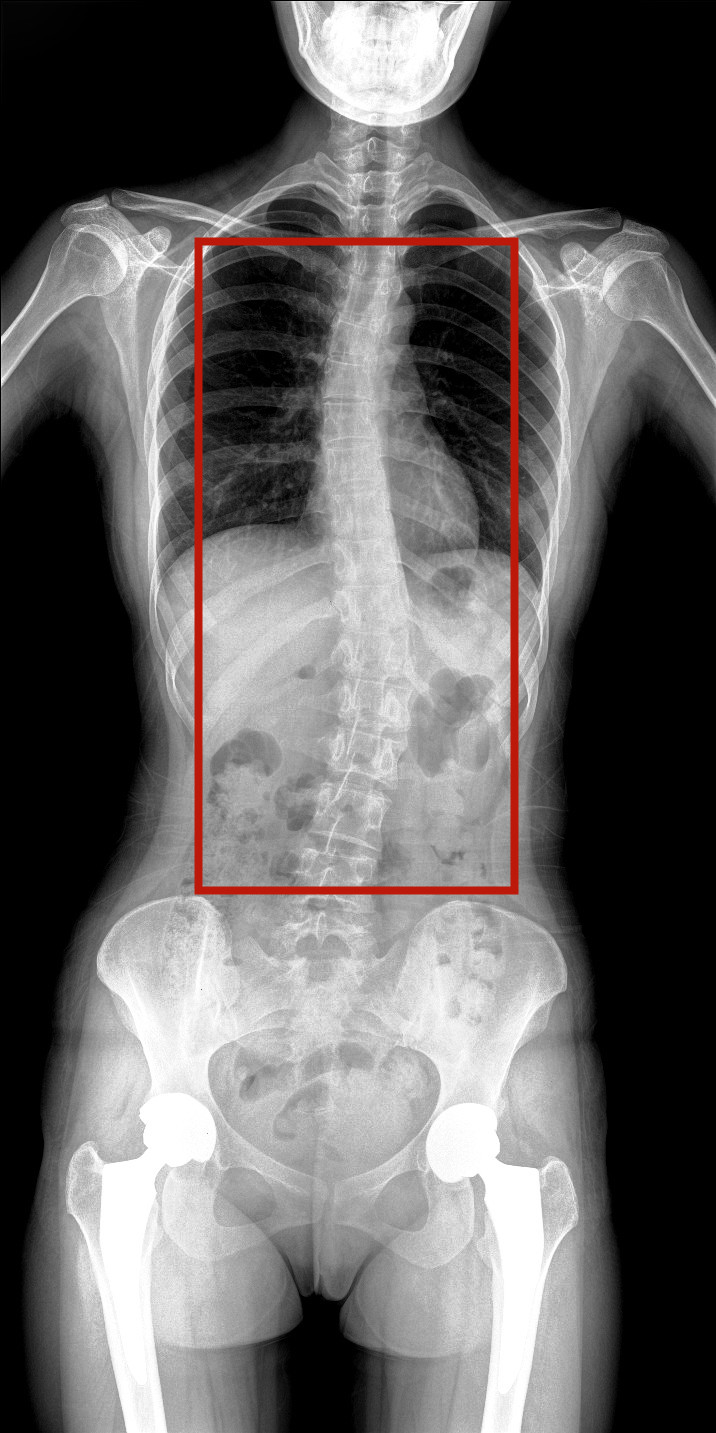

病情描述:患者,女,23歲,免疫系統(tǒng)畸變導致的脊柱側彎

虛線框示患者脊柱側彎明顯

脊柱圖像范圍包含脊椎、雙側肩部及骨盆。片內頸椎、胸椎、腰椎、骶椎、雙肩及骨盆重組影像結構清晰,對比度高,對位、對線好,接緣區(qū)無重疊、遺漏、縫隙。能夠滿足臨床測量脊柱Cobb角及臨床人體平衡線等指標的測量,整體上能對全脊柱進行觀察診斷。